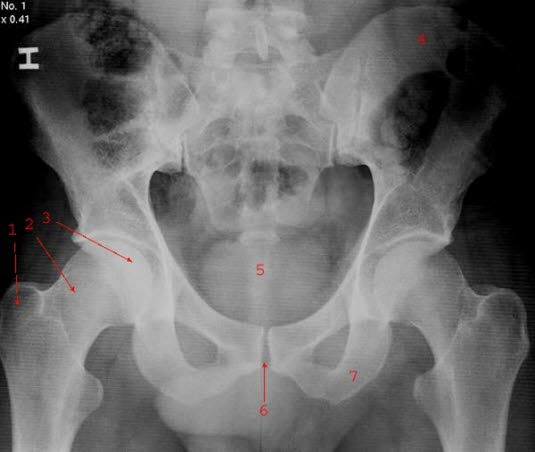

Hofteskålen (acetabulum) er den delen av hofteleddet som hører til bekkenbeinet. Det er bekkenets leddflate mot lårbeinet, som er som navnet sier, skålformet.

På sykehuset stilles diagnosen på grunnlag av både sykehistorien og bildediagnostikk. I første omgang er det kjennskap til skadetypen, eventuelle smerter eller manglende evne til å bevege i hofteleddet eller å trå på benet, som vil vekke mistanke om brudd i hoften. Deretter tas røntgenbilder både forfra og fra siden. I mange tilfeller kan det være nødvendig å ta CT-bilder også, for å få en mest mulig presis fremstilling av bruddskaden(e).

Røntgen av normalt bekkenSiden det vanligvis dreier seg om en høyenergi ulykke, vil den skadede bli grundig undersøkt med henblikk på å avdekke eventuelle andre skader.